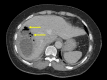

Figure 3. An axial contrast computed tomography image showing a large liver abscess with pockets of gas (arrows) consistent with a GFPLA

GFPLA: gas-forming pyogenic liver abscess